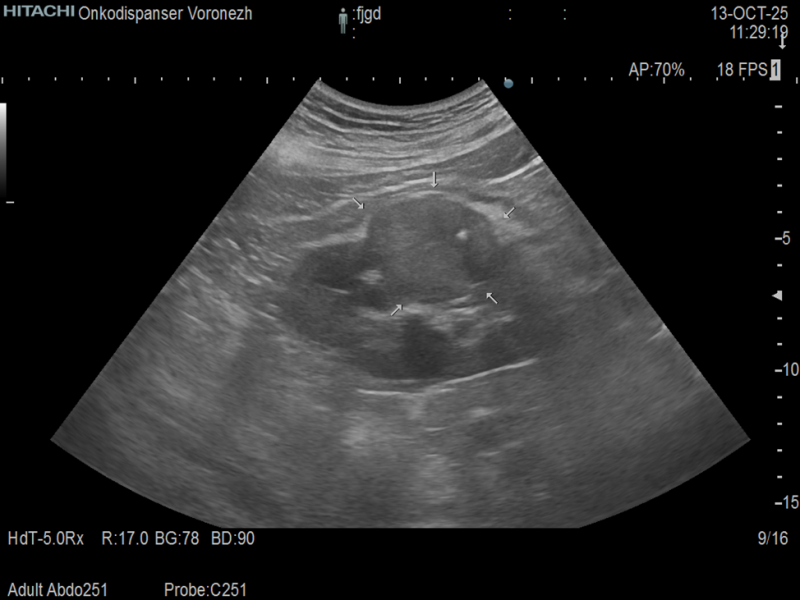

• как случайная находка при диспансерном проведении ультразвукового исследования (УЗИ), компьютерной (КТ) и магнитно-резонансной (МРТ) томографий;

• как случайная находка при поиске неурологического заболевания (например, если при КТ легких в срез попал верхний сегмент почки с имеющейся опухолью; или когда выполняется УЗИ при желчекаменной болезни и выявляется опухоль правой почки);

• если наличие изменений в анализах крови и/или мочи послужило основанием к проведению УЗИ почек.